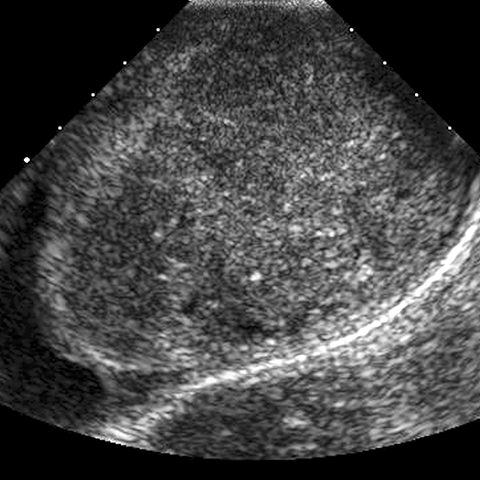

28-year-old man with left-sided testicular swelling. [1 of 2]